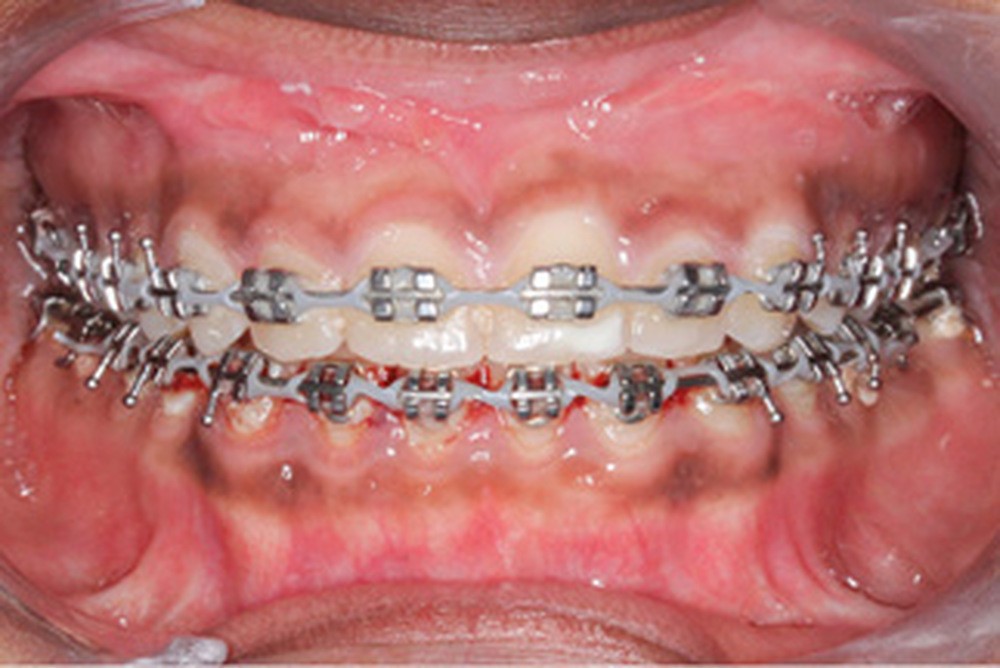

Un protocole ortho-chirurgical en chirurgie première a été retenu. Les étapes de traitement ont été les suivantes : motivation à l’hygiène bucco-dentaire et rééducation des fonctions, puis pose de l’appareil multi-attache edgewise conventionnel avec des arcs aciers .016x.022 passifs adaptés aux deux formes d’arcades, et enfin avancée de 6 mm et génioplastie d’avancée sur ces mêmes arcs.

Lors de la réévaluation post-chirurgicale, l’examen exo-buccal montre peu de changement, excepté l’occlusion et l’harmonie labiales retrouvées. Le surplomb et le recouvrement sont normalisés et le brossage amélioré. Les formes d’arcade sont concordantes, les médianes inter-incisives recentrées et les molaires et canines en classe I.